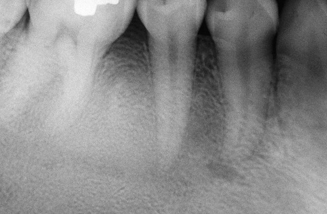

periapical cemento-osseous dysplasia

focal cemento-osseous dysplasia